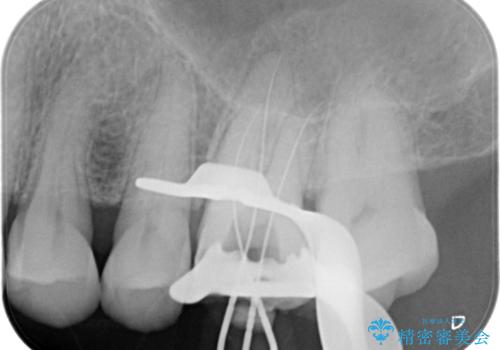

根管治療にはラバーダムシートをつけて行うことが大切です。マイクロスコープを使用し治療を行いました。治療後、歯の痛みは消失し、とても満足していただきました。